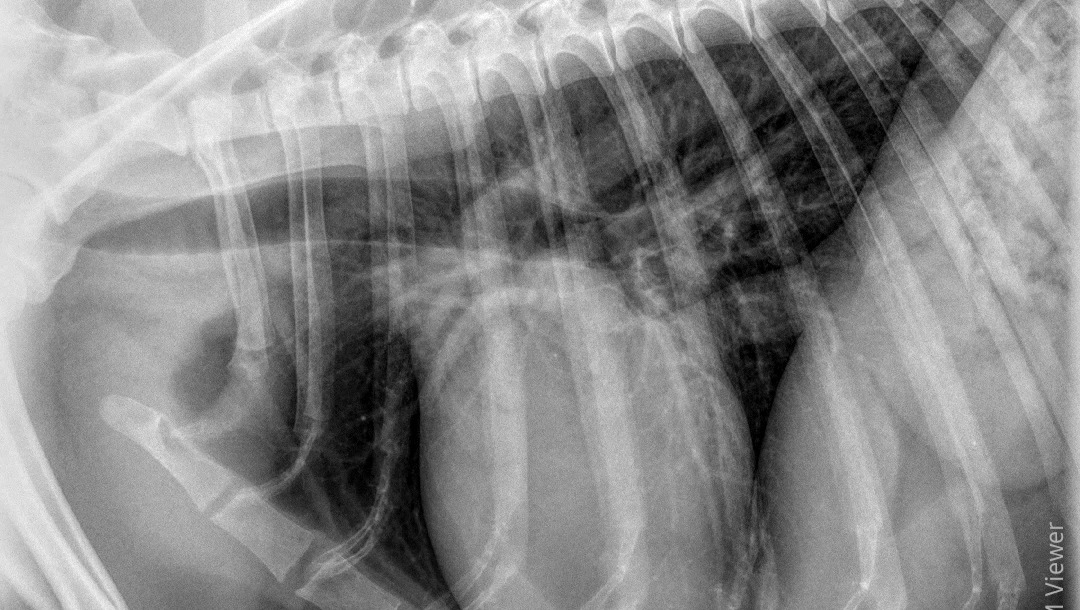

He went in on December 4th, was sedated, and got an X-ray done on his head and chest. This told us nothing aside from yes - there is a hole in his bone. There's no mass or tumor, there's no fuzziness on the edges of the hole, and his lungs look good. My vet, who has been seeing Sage since I got him, doesn't believe it to be cancer, though he also said unilateral nosebleeds are rarely not cancer. But, X-rays can only pick up so much in terms of other possibilities - Could it be a foreign body like a foxtail? A fungal infection like Aspergillosis? Neither of those show up on X-ray.